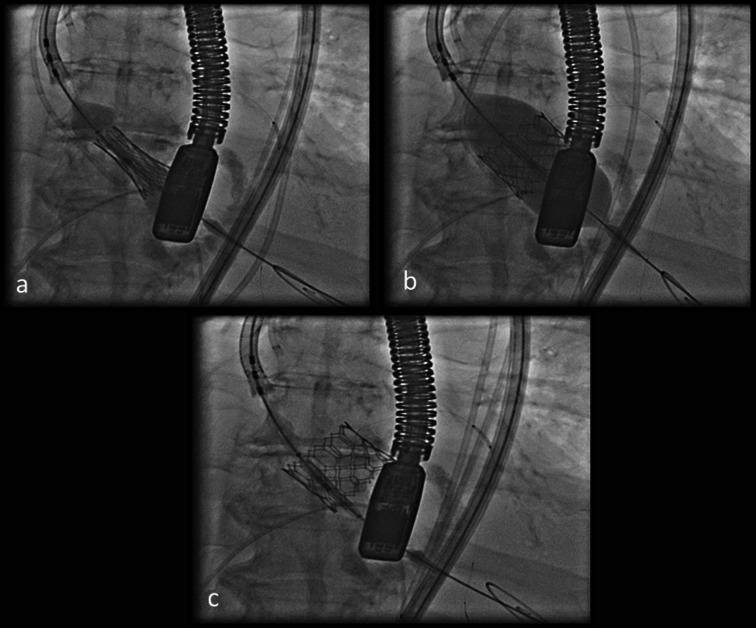

An 82-year-old woman with severe aortic valve stenosis (AS) and a significant proximal right coronary artery (RCA) stenosis presented with decompensated heart failure and acute kidney injury. She was treated with intravascular ultrasound (IVUS)-guided percutaneous coronary intervention (PCI) and trans-oesophageal echocardiography (TOE)-guided transcatheter aortic valve replacement (TAVR).

一名82岁女性,患有严重主动脉瓣狭窄(AS)且右冠状动脉(RCA)近端存在明显狭窄,出现失代偿性心力衰竭和急性肾损伤。她接受了血管内超声(IVUS)引导下的经皮冠状动脉介入治疗(PCI)以及经食管超声心动图(TOE)引导下的经导管主动脉瓣置换术(TAVR)。